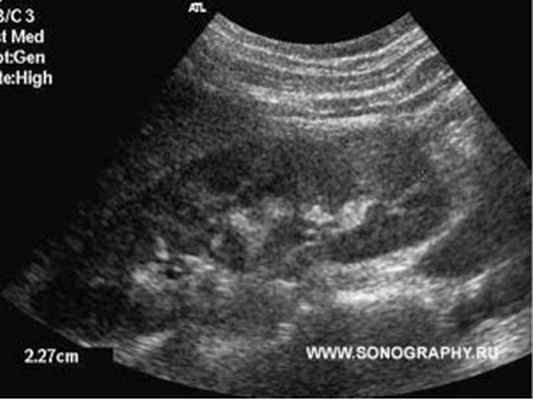

Повышение температуры тела, боли в спине или боку, болезненное мочеиспускание. Эти симптомы могут свидетельствовать о развитии послеродового пиелонефрита, то есть воспаления почек. Критическими периодами для развития послеродового пиелонефрита врачи считают 4-6 и 12-14 сутки послеродового периода. Развитие заболевания связано с попаданием инфекции в мочевыводящие пути из половых путей. Чаще всего заболевание развивается у родильниц, в моче которых во время беременности обнаруживали небольшое количество бактерий. В постановке диагноза врачу помогают ультразвуковое исследование почек и мочевого пузыря и анализ мочи.

- УЗИ мочевыделительной системы, с оценкой кровотока;

УЗИ — показывает анатомическую структуру органов, состояние стенок, наличие уплотнений и расширений в чашечках и лоханках почек. Для дифференциации первичного пиелонефрита от вторичного может проводиться хромоцистоскопия. Это метод обследования почек и верхних мочевых путей, по которому определяется, есть ли препятствия в движении мочи.